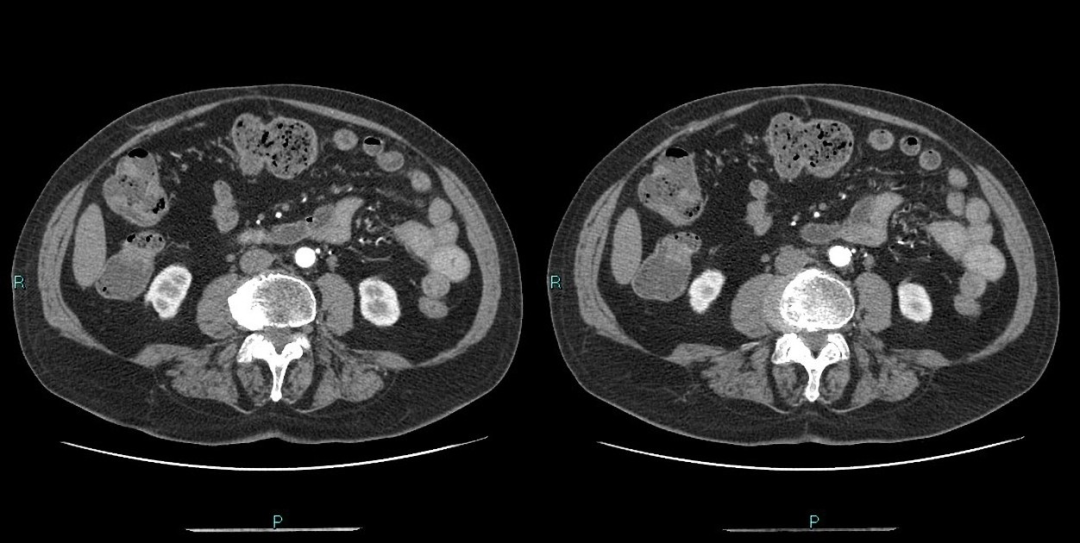

患者男 35 岁 因头疼、高血压入院,拟高血压病因待查;

CT 平扫发现左肾上腺可见类圆形稍低密度影,建议进一步检查;

然后完善增强扫描;

咦,不对啊,增强扫描不支持嗜铬细胞瘤的表现啊。

咦,大家有没有发现不对的地方?

大家有没有注意到双侧肾动脉的情况?

这个肾动脉怎么看上去和平时的不一样啊;